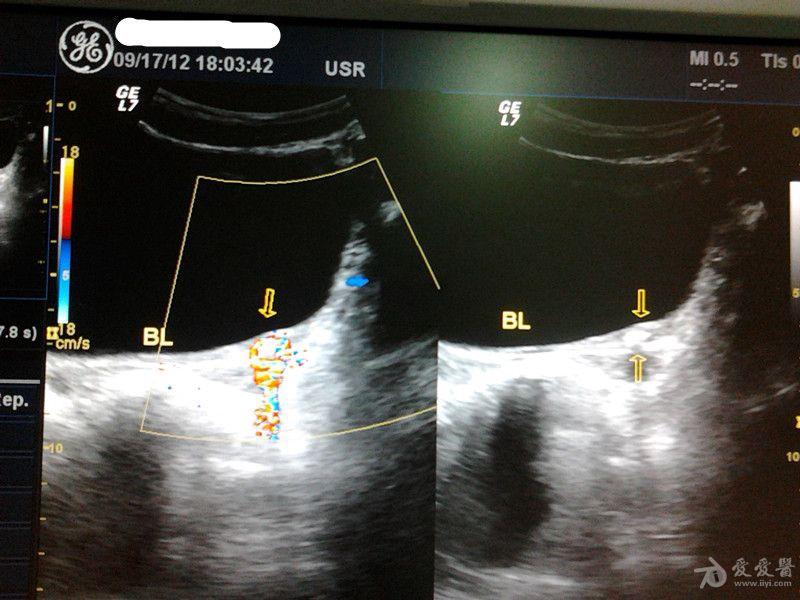

输尿管末端结石 超声医学讨论版 爱爱医医学论坛 爱爱医医学网